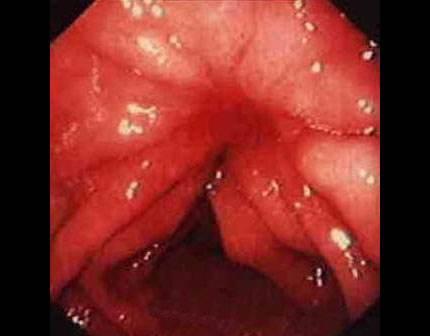

痔瘡癌變的10個前兆

1、痔瘡疼痛加?。褐摊徎颊呷绺杏X疼痛逐漸加劇,可能是癌變的一個信號。

2、痔瘡出血:長期痔瘡出血,尤其是出現(xiàn)持續(xù)性出血時,應警惕癌變的可能。

3、痔瘡體積變化:如痔瘡體積在短時間內迅速增大,可能是癌變的征兆。

4、排便習慣改變:如排便頻率增加或減少,以及出現(xiàn)便秘與腹瀉交替的情況,可能與痔瘡癌變有關。

5、肛門不適:出現(xiàn)肛門墜脹、異物感等癥狀時,應考慮痔瘡癌變的可能性。

10、便血顏色變化:如便血顏色由鮮紅色變?yōu)榘导t色或混合有黏液,應引起重視。